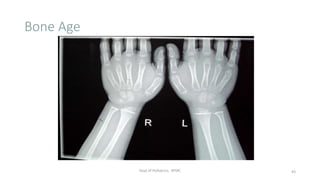

Bone Age

Dept of Pediatrics, AFMC 43

• What are the radiographs that you will prefer to assess bone age at

- < 1 yr

- 1 – 12 yrs

- > 12 yrs

Bone Age Estimation

• X-Ray left hand with wrist

• Scoring system of each of 20 individual hand bones

(Tanner-Whitehouse Method, TW2), a technique that has

been adapted for computerized assessment

• BA is a better predictor pubertal milestones than CA